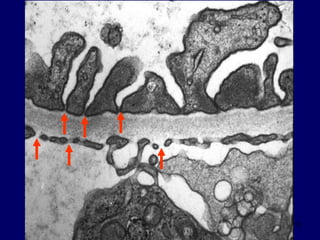

Distal Tubules

20

21

Tubule

Distal Tubule

PTC - Endo

TBM

22